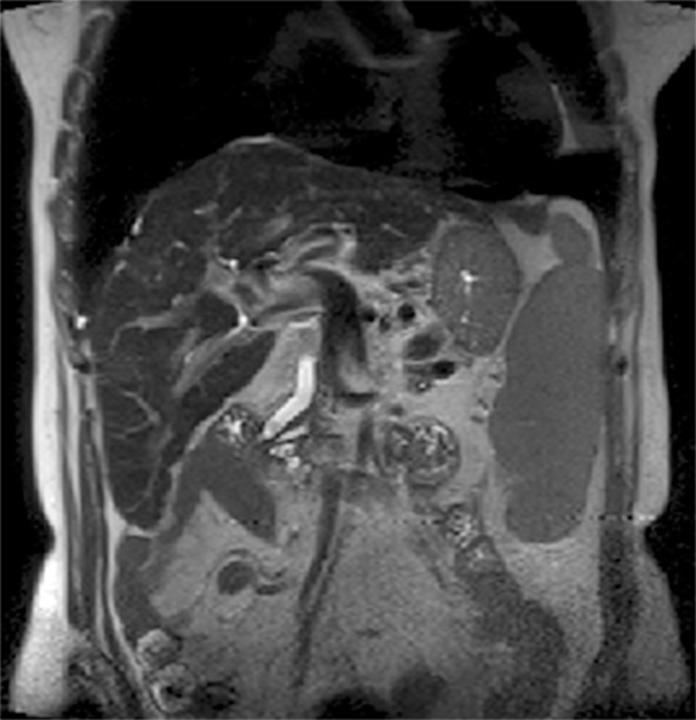

3特斯拉磁共振成像中偶然发现的胰腺囊肿的患病率

Prevalence of incidental pancreatic cysts on 3 tesla magnetic resonance.

To ascertain the prevalence of pancreatic cysts detected incidentally on 3-Tesla magnetic resonance imaging (MRI) of the abdomen and correlate this prevalence with patient age and gender; assess the number, location, and size of these lesions, as well as features suspicious for malignancy; and determine the prevalence of incidentally detected dilatation of the main pancreatic duct (MPD).

Retrospective analysis of 2,678 reports of patients who underwent abdominal MRI between January 2012 and June 2013. Patients with a known history of pancreatic conditions or surgery were excluded, and the remaining 2,583 reports were examined for the presence of pancreatic cysts, which was then correlated with patient age and gender. We also assessed whether cysts were solitary or multiple, as well as their location within the pancreatic parenchyma, size, and features suspicious for malignancy. Finally, we calculated the prevalence of incidental MPD dilatation, defined as MPD diameter ≥ 2.5 mm.

Pancreatic cysts were detected incidentally in 9.3% of patients (239/2,583). The prevalence of pancreatic cysts increased significantly with age (p<0.0001). There were no significant differences in prevalence between men and women (p=0.588). Most cysts were multiple (57.3%), distributed diffusely throughout the pancreas (41.8%), and 5 mm or larger (81.6%). In 12.1% of cases, cysts exhibited features suspicious for malignancy. Overall, 2.7% of subjects exhibited incidental MPD dilatation.

In this sample, the prevalence of pancreatic cysts detected incidentally on 3T MRI of the abdomen was 9.3%. Prevalence increased with age and was not associated with gender. The majority of cysts were multiple, diffusely distributed through the pancreatic parenchyma, and ≥ 5 mm in size; 12.1% were suspicious for malignancy. An estimated 2.7% of subjects had a dilated MPD.